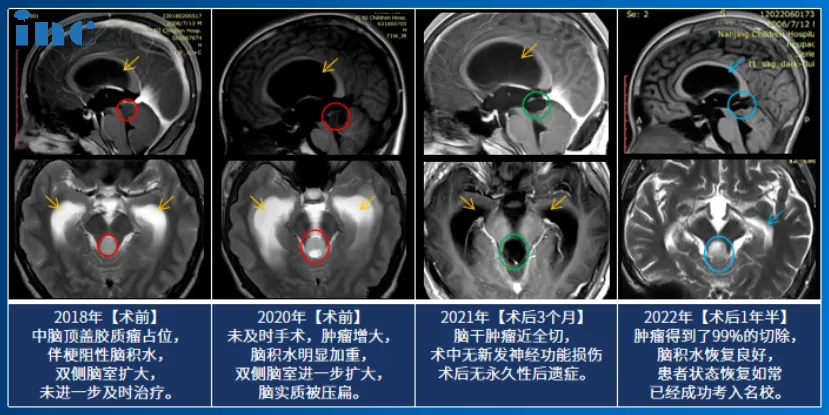

2020年11月,14岁的小永因患脑干-中脑顶盖部位的毛细胞型星形细胞瘤住进医院,MRI影像检查发现松果体区占位伴幕上脑室扩张积水,病灶有明显强化生长迹象。2年前父母带他去过国内多家知名医院,可是得到的治疗意见都是:“手术风险太大,无症状时不必着急手术。”父母因此一直没敢给孩子选择手术治疗,直到孩子的病情越来越严重,影像检查发现小永的脑干-中脑顶盖占位伴幕上脑室扩张积水,再不进行手术,孩子可能会面临着更大的风险……

治疗过程:小永父亲在医生朋友的推荐下联系到INC德国巴特朗菲教授进行国际诊疗咨询。巴教授表示,小永已有很明显的手术指征,如果能及时接受手术,脑脊液通道可以通过肿瘤的切除而得到恢复。小永父母决定带孩子赴德国接受巴教授的手术治疗。术中教授在保全患者正常功能神经和脑干等重要脑组织的前提下,完成肿瘤近全切手术,术后无新发永久性后遗症。